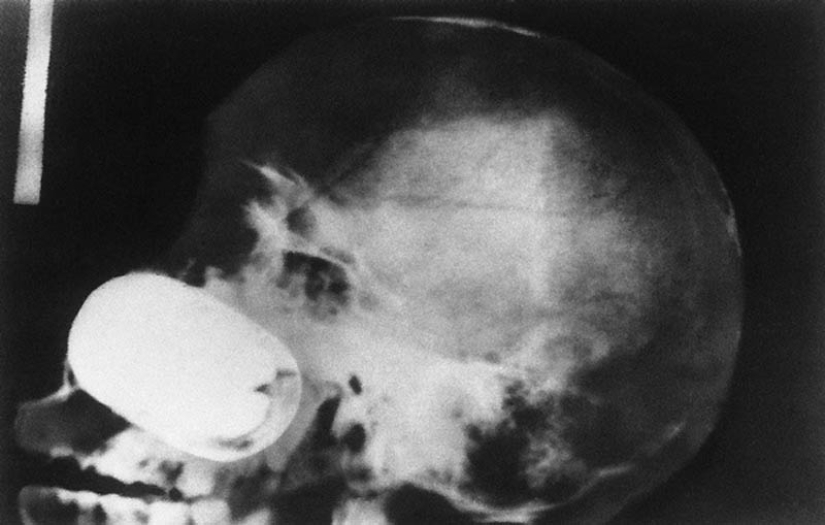

16. A grenade in the prisoner's skull.